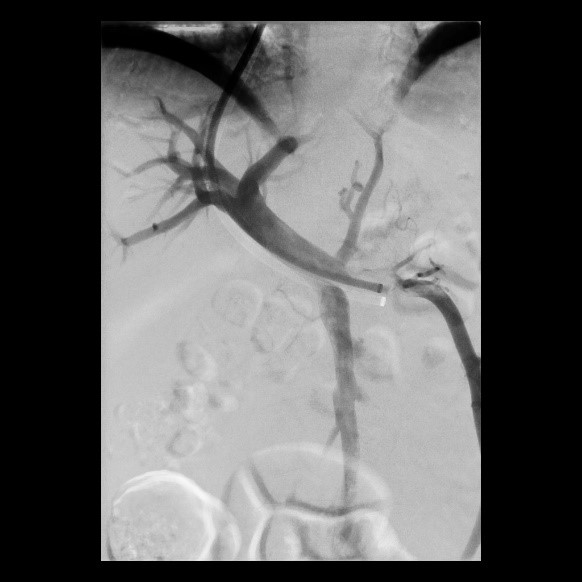

Erfolgreiche Implantation eines transjugulären intrahepatischen portosystemischen Shunts (TIPSS) bei Leberzirrhose und refraktärem Aszites. Implantation eines Stentgrafts

(Bild 4 von 4)